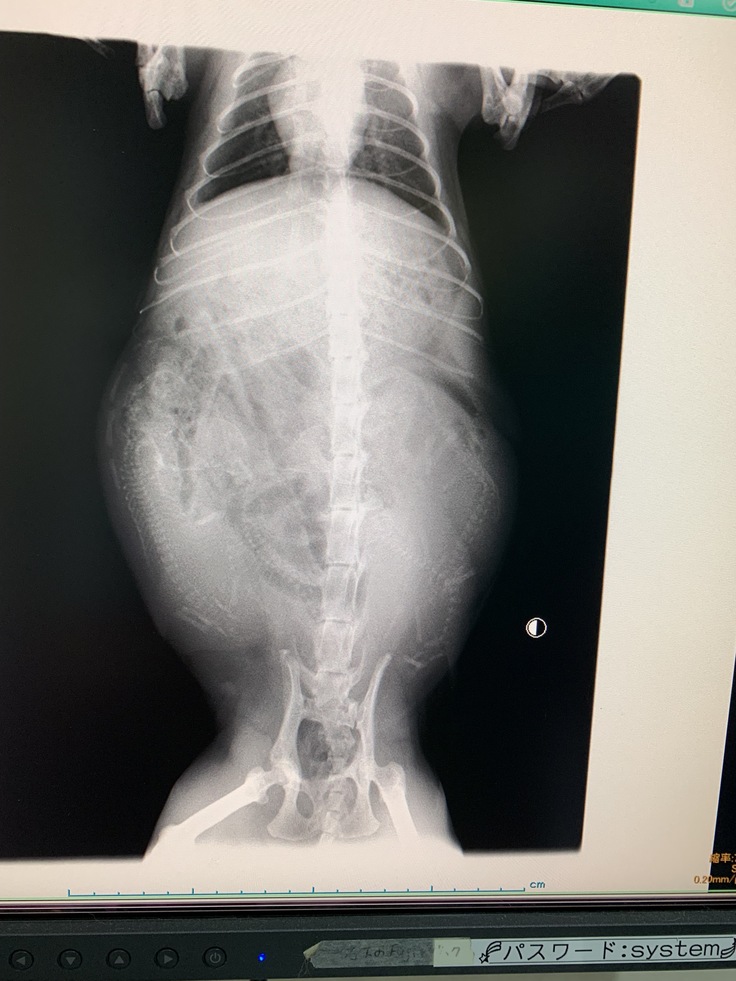

しかし幼いはずのハイジの胸が張ってきました。まさか?・・・との声があがりましたが、「心配しすぎでは?」と一笑に付していたのです。しかしその「まさか」でした。

幼猫ハイジは妊娠していたのです。